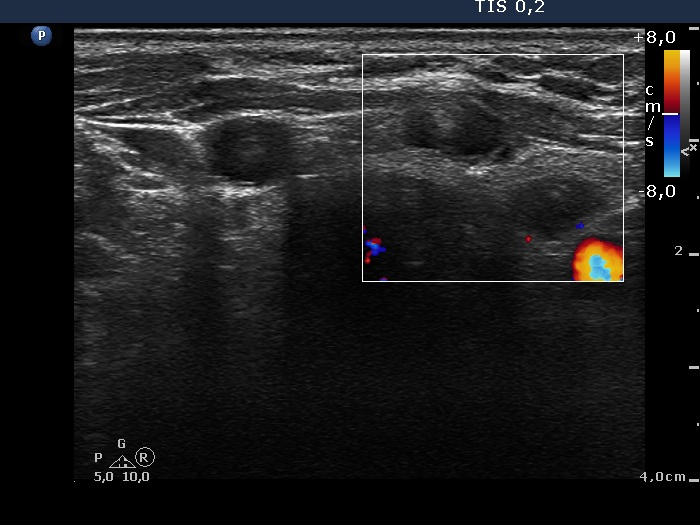

Isthmus and left lobe, transverse view, color Doppler mode. The lesion in the isthmus is avascular